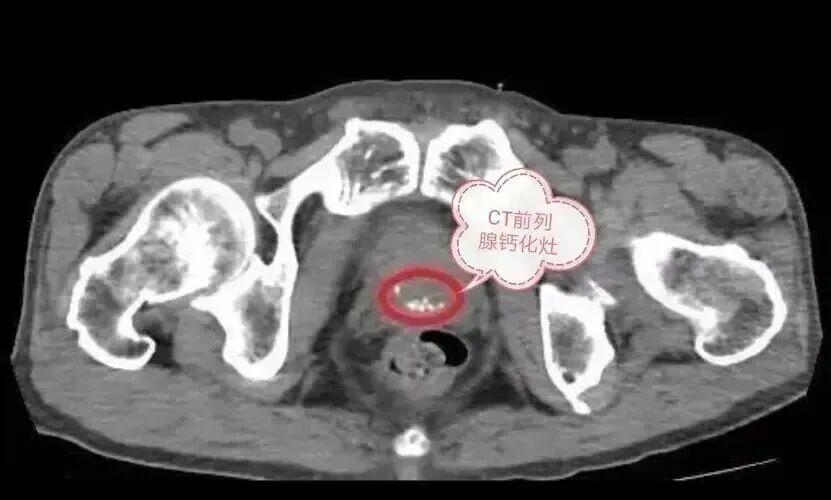

10 前列腺钙化

• 这可能是每一个男人都遇到的问题,前列腺钙化的形成,可能源于之前得过前列腺炎,康复后遗留下来的疤痕

• 如果没有排尿困难,只需要定期复查就可以,不用过于担心,不是啥大事。